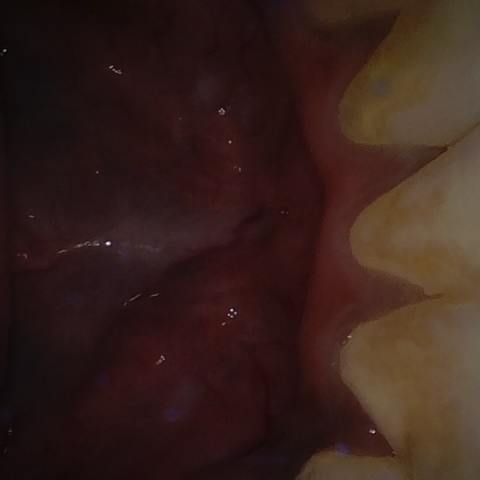

Annotated as "Good"